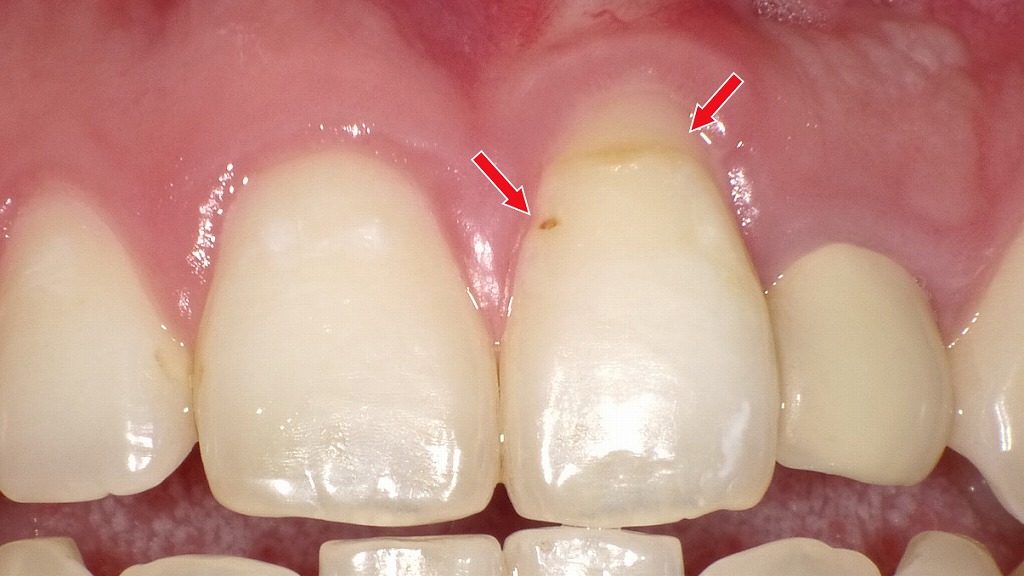

歯と歯の間の黒い点は要注意|レントゲンで発見できる“隠れ虫歯”

赤矢印が示すように、歯と歯の間(コンタクト部)の初期虫歯は、肉眼ではほとんど確認できません。レントゲンを撮影することで、エナメル質内部の透過像として虫歯を早期に発見できます。見た目に穴がなくても進行している場合があるため、定期的なレントゲン検査は非常に有効です。